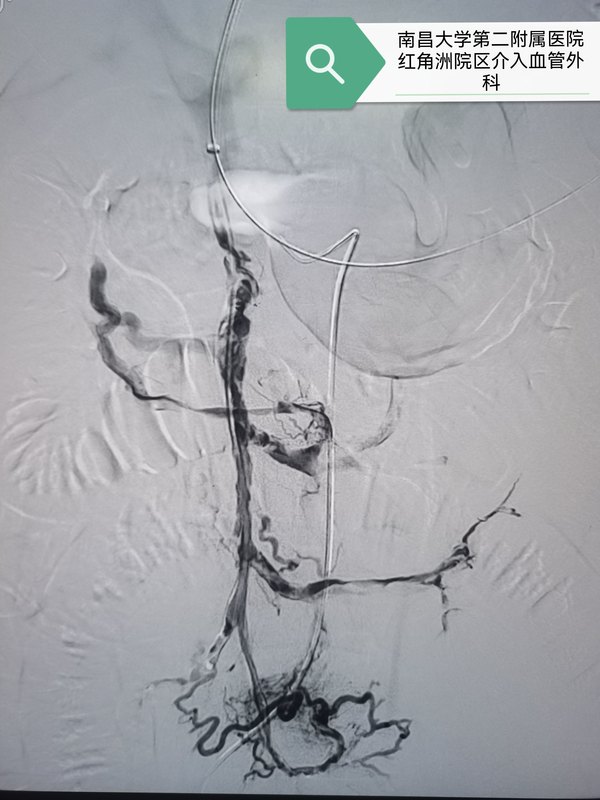

經(jīng)腸系膜上動(dòng)脈置管溶栓治療門靜脈血栓案例分享

患者男性43歲,因反復(fù)腹痛半個(gè)月,加重4天于2024年2月28日急診入院,當(dāng)天ct提示門脈主干及腸系膜上靜脈廣泛血栓。患者血栓負(fù)荷大,腹痛明顯,及時(shí)抗凝治療同時(shí)急診采取經(jīng)腸系膜上動(dòng)脈置管溶栓治療。7天后復(fù)查見門脈血栓明顯減少?;颊甙Y狀基本消失,拔除溶栓導(dǎo)管,出院繼續(xù)口服利伐沙班抗凝。2個(gè)月后復(fù)查:繼續(xù)密切觀察,繼續(xù)抗凝治療,利伐沙班20毫克,qd。點(diǎn)評(píng):門脈血栓臨床多見,治療方案選擇也存在一定的爭議,我們既往采取抗凝治療聯(lián)合經(jīng)腸系膜上動(dòng)脈置管溶栓治療不同程度門脈血栓患者均取得良好效果。此患者就診時(shí)候血栓負(fù)荷較大且腹脹腹痛癥狀明顯,但是沒有出血及腸壞死表現(xiàn),故暫不考慮tips途徑,但考慮單純抗凝效果較慢,我們采取腸系膜上動(dòng)脈置管溶栓加抗凝的方案。七天后復(fù)查血栓明顯減少,且患者腹痛癥狀基本消失,故停止溶栓,繼續(xù)口服利伐沙班抗凝治療??鼓齼蓚€(gè)月后復(fù)查,血栓基本消失,繼續(xù)抗凝治療。這個(gè)案例或許提示即使在血栓負(fù)荷較重的患者采取這個(gè)方案依然可能取得滿意的療效,值得更多嘗試。對(duì)于門脈血栓負(fù)荷較重的患者,介入同道曾嘗試經(jīng)皮經(jīng)肝穿刺取栓及置管溶栓的方案,近年來也有不少同道采取直接tips通道抽栓及溶栓的方案,這兩個(gè)方案風(fēng)險(xiǎn)費(fèi)用均遠(yuǎn)高于經(jīng)腸系膜上動(dòng)脈置管溶栓,但是效果是否優(yōu)于經(jīng)腸系膜上動(dòng)脈置管溶栓仍然存在爭議。根據(jù)肝硬化門靜脈血栓管理專家共識(shí)(2020年,上海)引用一項(xiàng)隨機(jī)對(duì)照試驗(yàn)比較了經(jīng)腸系膜上動(dòng)脈持續(xù)泵入尿激酶(劑量為15000IU·kg?1·d?1)與TIPS治療肝硬化PVT的療效差異,雖然兩組間的門靜脈主干血栓的再通率相近,但溶栓組的腸系膜上靜脈及脾靜脈血栓的再通率顯著高于TIPS組,且肝性腦病發(fā)生率明顯更低。提示該共識(shí)意見似乎更傾向于推薦采取經(jīng)腸系膜上動(dòng)脈置管溶栓的方案。